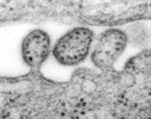

(바이러스) Lassa virus

출처:http://phil.cdc.gov/phil/details.aspID#8699, CDC/ C. S. Goldsmith, D. Auperin

• 특 성:Arenaviridae과, Arenavirus속, 부정형이나 대체로 구형, (-)ssRNA 바이러스, 피막 있음